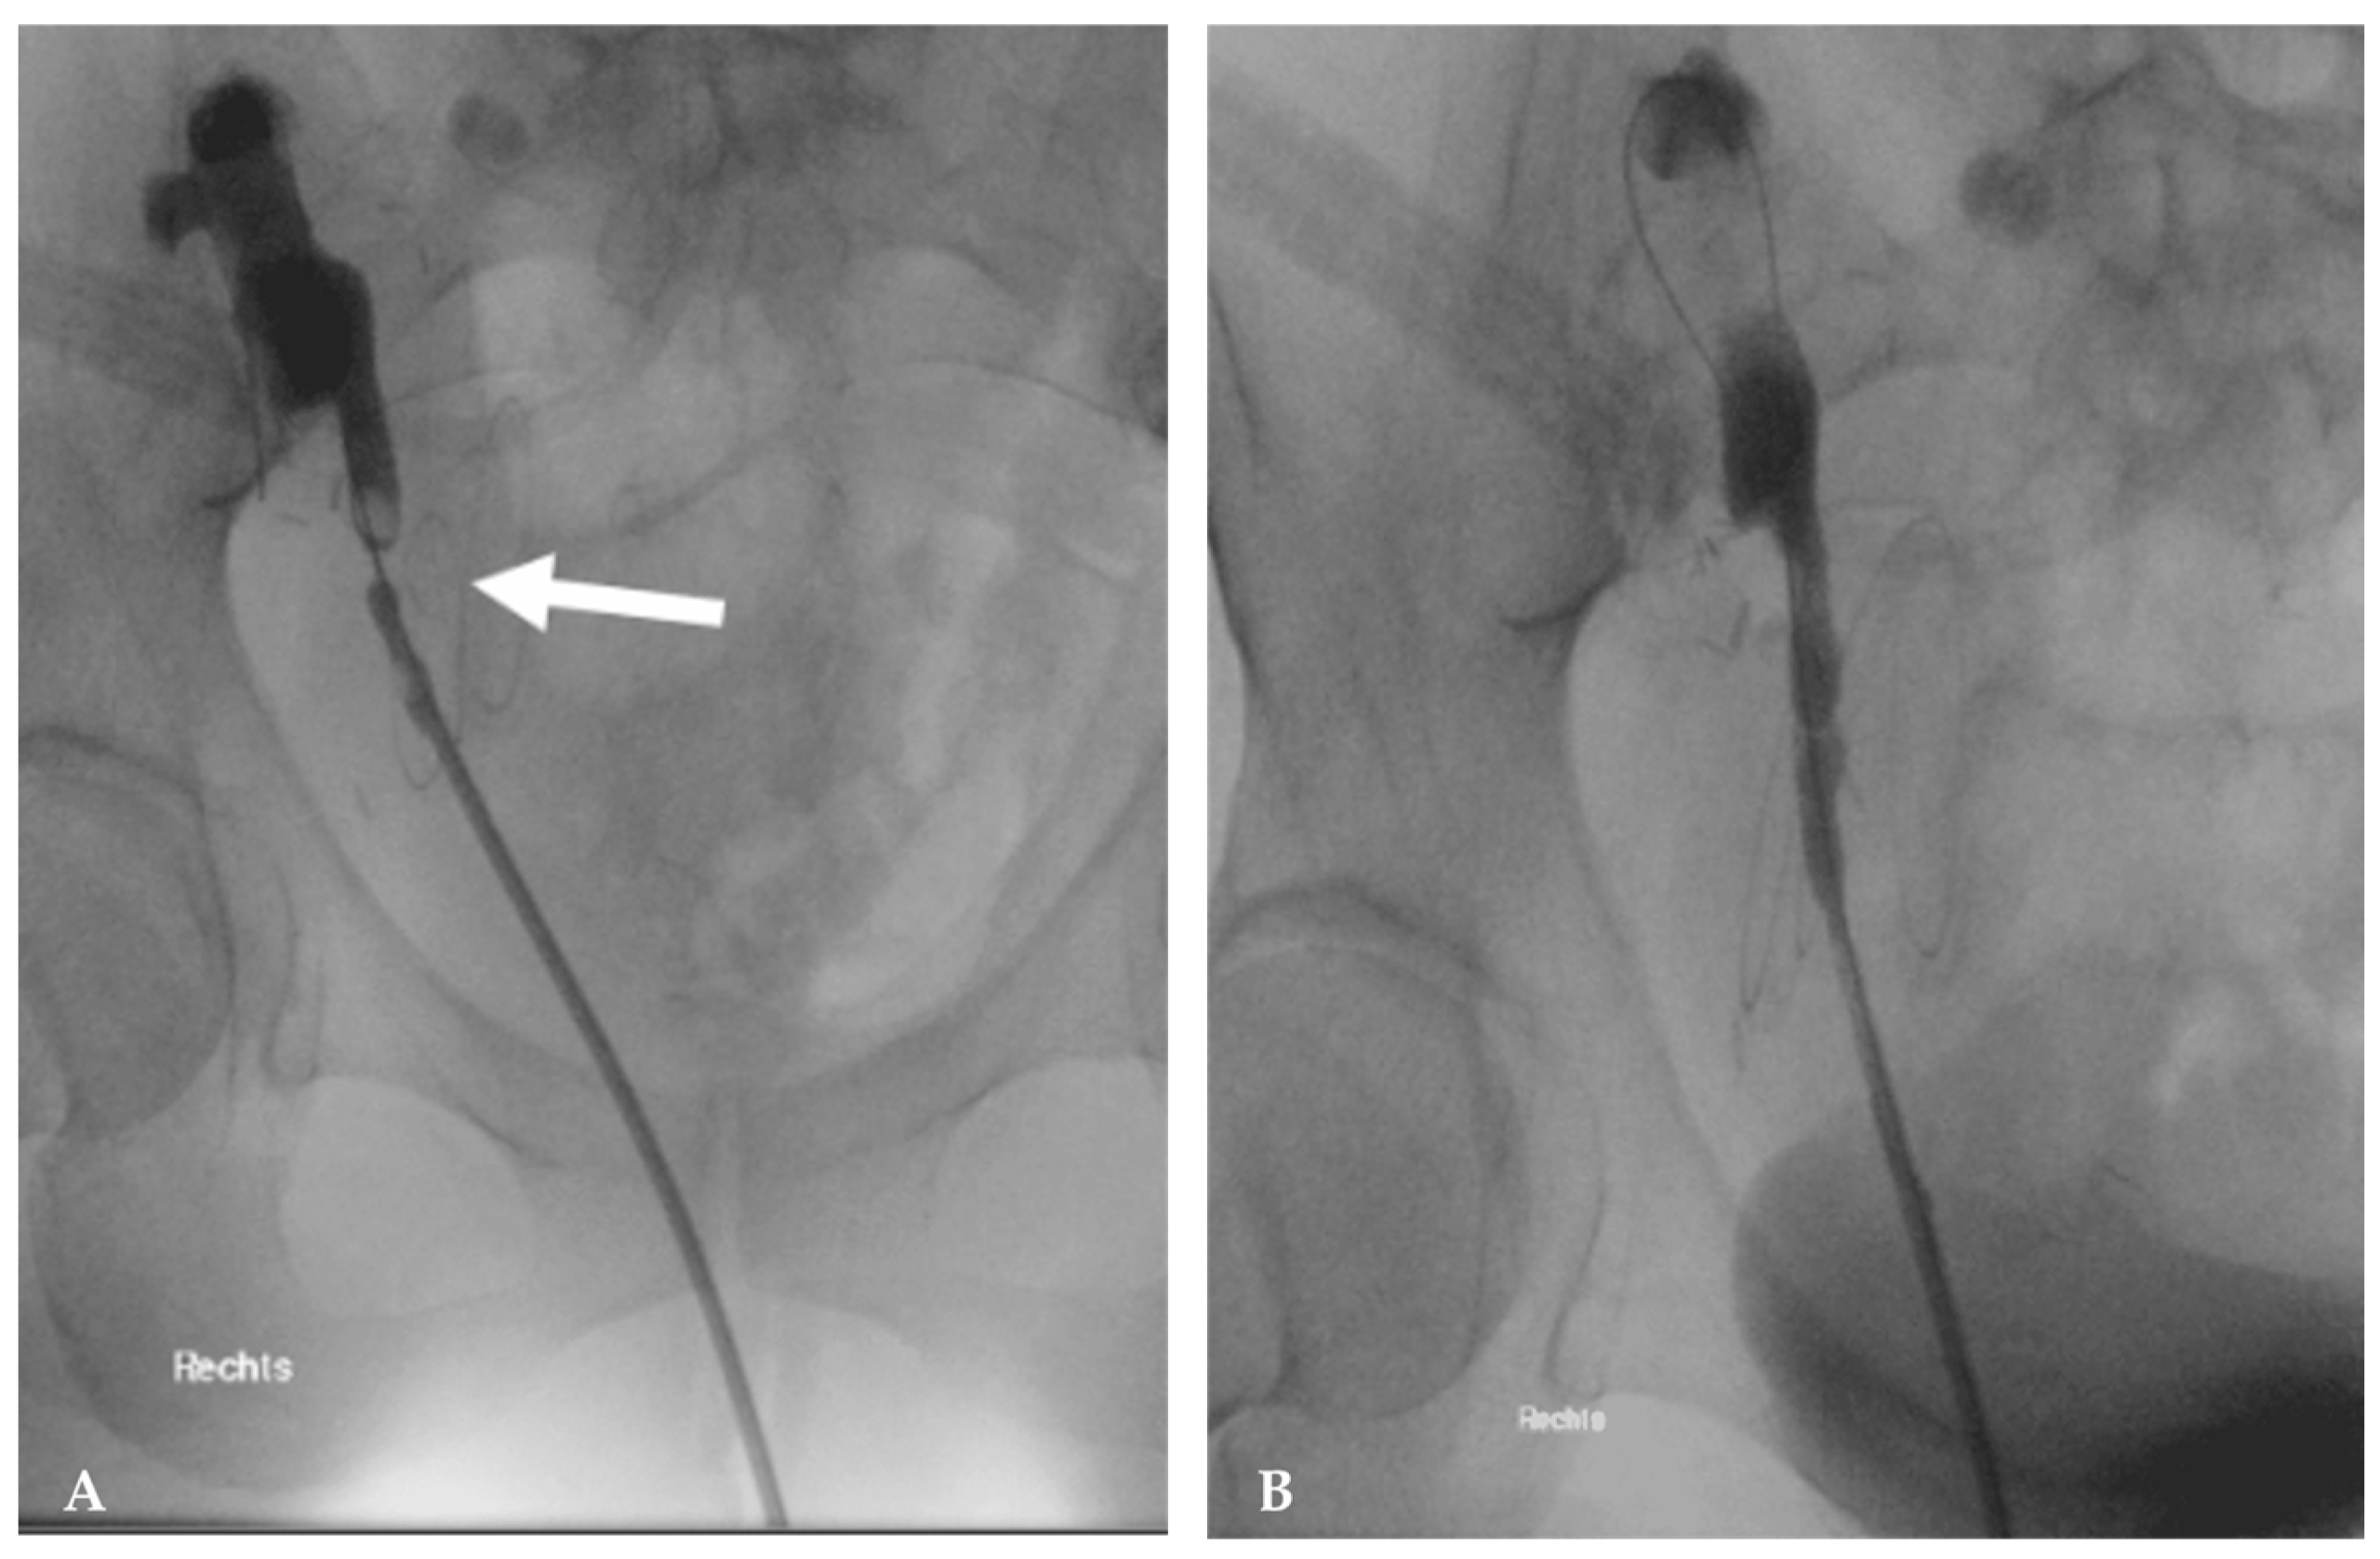

Arterial Stenosis

- Ghirardo, G.; De Franceschi, M.; Vidal, E.; Vidoni, A.; Ramondo, G.; Benetti, E.; Motta, R.; Ferraro, A.; Zanon, G.F.; Miotto, D.; et al. Transplant renal artery stenosis in children: Risk factors and outcome after endovascular treatment. Pediatr. Nephrol. 2014, 29, 461–467. [Google Scholar] [CrossRef]

- Dimitrijeva, B.S.; Djukic, M.; Gojkovic, I.; Nikolovski, S.S.; Sagic, D.; Pavicevic, P.; Radovic, T.; Vasic, D.; Radmili, O.; Stefanovic, I.; et al. Diagnosis and Endovascular Management of Transplant Renal Artery Stenosis: A Retrospective Two-Decade Study. Cureus 2025, 17, e80393. [Google Scholar] [CrossRef]